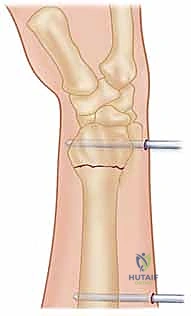

| المثبت الخارجي (External Fixator) | إطار معدني خارج الجسم يتصل بالعظام عبر مسامير تخترق الجلد بعيداً عن منطقة الكسر لتثبيته. | الكسور المفتتة الممتدة للمفصل، الكسور المفتوحة (مع جروح جلدية)، التورم الشديد الذي يمنع الجراحة المفتوحة. | يحافظ على طول العظم، يقلل تلف الأنسجة الرخوة في منطقة الكسر. | الإزعاج من وجود جهاز خارجي، خطر التهاب مسار المسامير، يتطلب عناية يومية بالتنظيف. |